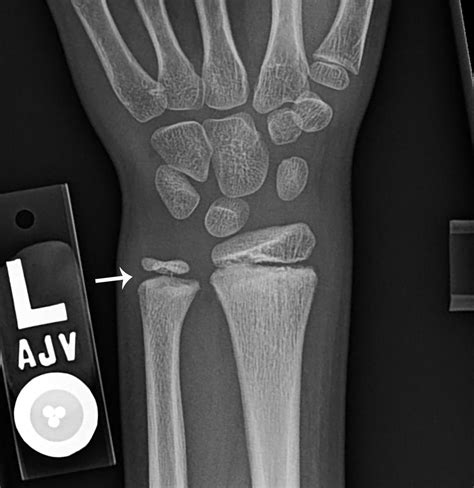

Distal Radius Fracture Sudden onset after trauma. Sharp pain, severe swelling, bruising.

DRUJ Instability Bone shifts during rotation. Clicking, popping sensation, instability.

If you notice your wrist bone sticking out and it is accompanied by functional limitations, it is time to consult an orthopedist or a physical therapist. A medical professional will typically perform a physical examination to check for stability and may order diagnostic imaging, such as an X-ray, to rule out fractures, ligament tears, or severe arthritis.